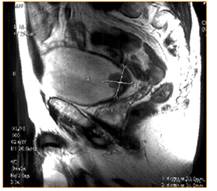

В последние время все активнее стали применять в клинической практике такие методы, как КТ и МРТ. Эти исследования показаны только после клинических, ультразвуковых и обычных рентгенологических и эндоскопических исследований, по данным которых формируется предварительный диагноз.

МРТ сочетает в себе лучшие свойства ультасонографии и РКТ. Чувствительность МРТ при распространении опухоли в клетчатку составляет 98%. Специфичность колеблется от 62 до 100% (Огнерубов Н.А. и соавт., 1999 г.). К недостаткам и ограничениям метода можно отнести относительную дороговизну исследования, продолжительность процедуры. МРТ имеет преимущество, по сравнению с РКТ в определении прорастания опухоли в клетчатку таза и окружающие органы. Несомненным преимуществами также являются: высокое контрастное разрешение (в 70 раз выше, чем при РКТ); возможность получения информационных данных по нескольким параметрам; отсутствие ионизирующего излучения. Производители МРТ-систем в настоящее время сделали основной упор на выпуск моделей с низкими (< 0,3 Т) и средними (от 0,3 до 0,5 Т) полями, которые отличаются от высокопольных (> 0,5 Т) МРТ-систем компактностью и экономичностью при удовлетворительном качестве изображений и значительно меньшей продажной и эксплуатационной стоимости.